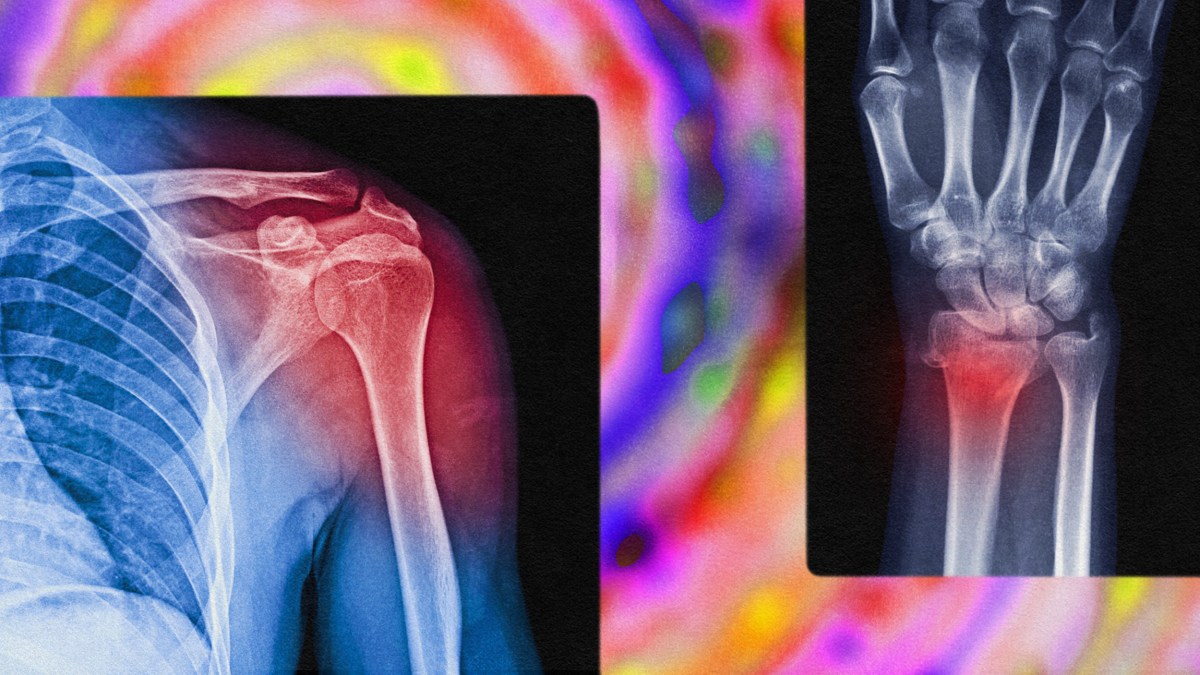

Chronic pain is defined as pain that persists beyond the usual recovery period or occurs with another condition. It may occur continuously or happen off and on. The most common manifestations of chronic pain are lower back pain, headache disorders, fibromyalgia, and neuropathic pain. People treated for chronic pain often undergo “pain management programs” that combine approaches from different fields to customize treatments.

Although it may be a reflection of ongoing physical health issues, chronic pain can also have deeply psychosomatic origins, reflecting the close relationship between mind and body.

“Neuropathic pain can lead to a centralized pain syndrome where the pain is still being processed in the brain,” says neuroanesthesiologist and neuroscientist Joseph Cichon, assistant professor in the Perelman School of Medicine at UPenn, in an article for UPenn’s website. “It’s as if there’s a loop that keeps playing over and over again, and this chronic form is completely divorced from that initial injury.”

Patrick Finan, Harold Carron Professor of Anesthesiology at the University of Virginia School of Medicine, told University of Virginia Today that the central nervous system may become “sensitized,” such that neurons continue firing pain signals long after the initial injury.

“In the case of chronic lower back pain, an MRI can show clear pathology in the spine,” he said. “Other times, and really quite often, patients will report they are experiencing real chronic lower back pain that’s not viewable by techniques like MRI. It’s not to diminish the pain people are reporting or to suggest they’re making it up. The resolution of our techniques does not always align with the reality of people’s pain.”